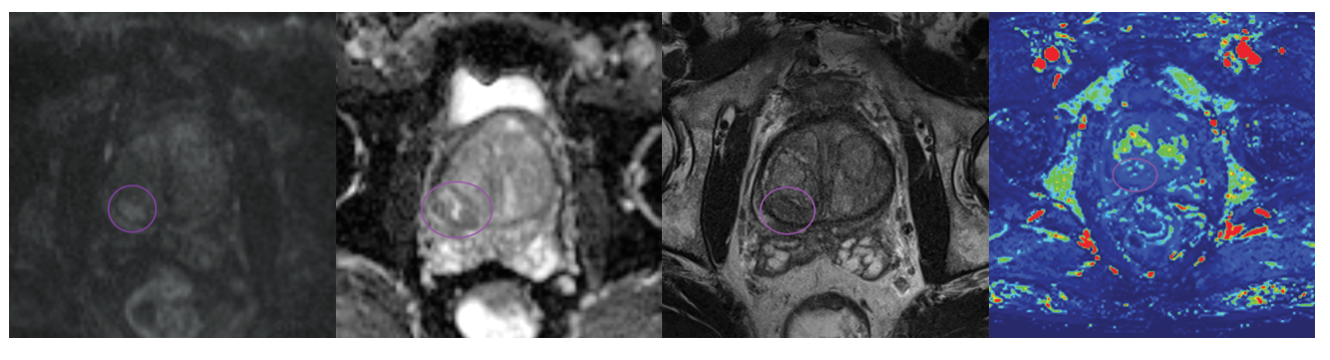

Đánh giá PI-RADS 3 . Phiên bản mới 2.1 (2023)

Các tổn thương này được phát hiện trên cộng hưởng từ (MRI) bằng cách sử dụng kết hợp các trình tự T2I , DWI/ADC và DCE.

• Gồm 1.481 tổn thương PI-RADS 3 được đánh giá riêng bằng cách sử dụng PI-RADS phiên bản 2.1.

-Có 164 (11,1%) chứa ung thư có ý nghĩa lâm sàng

-Phần lớn các tổn thương PI-RADS 3 là lành tính hoặc không có ý nghĩa lâm sàng (n=1.317, 88,9%).

Nhìn chung, nguy cơ ung thư có ý nghĩa lâm sàng đối với các tổn thương PI-RADS 3 là thấp.